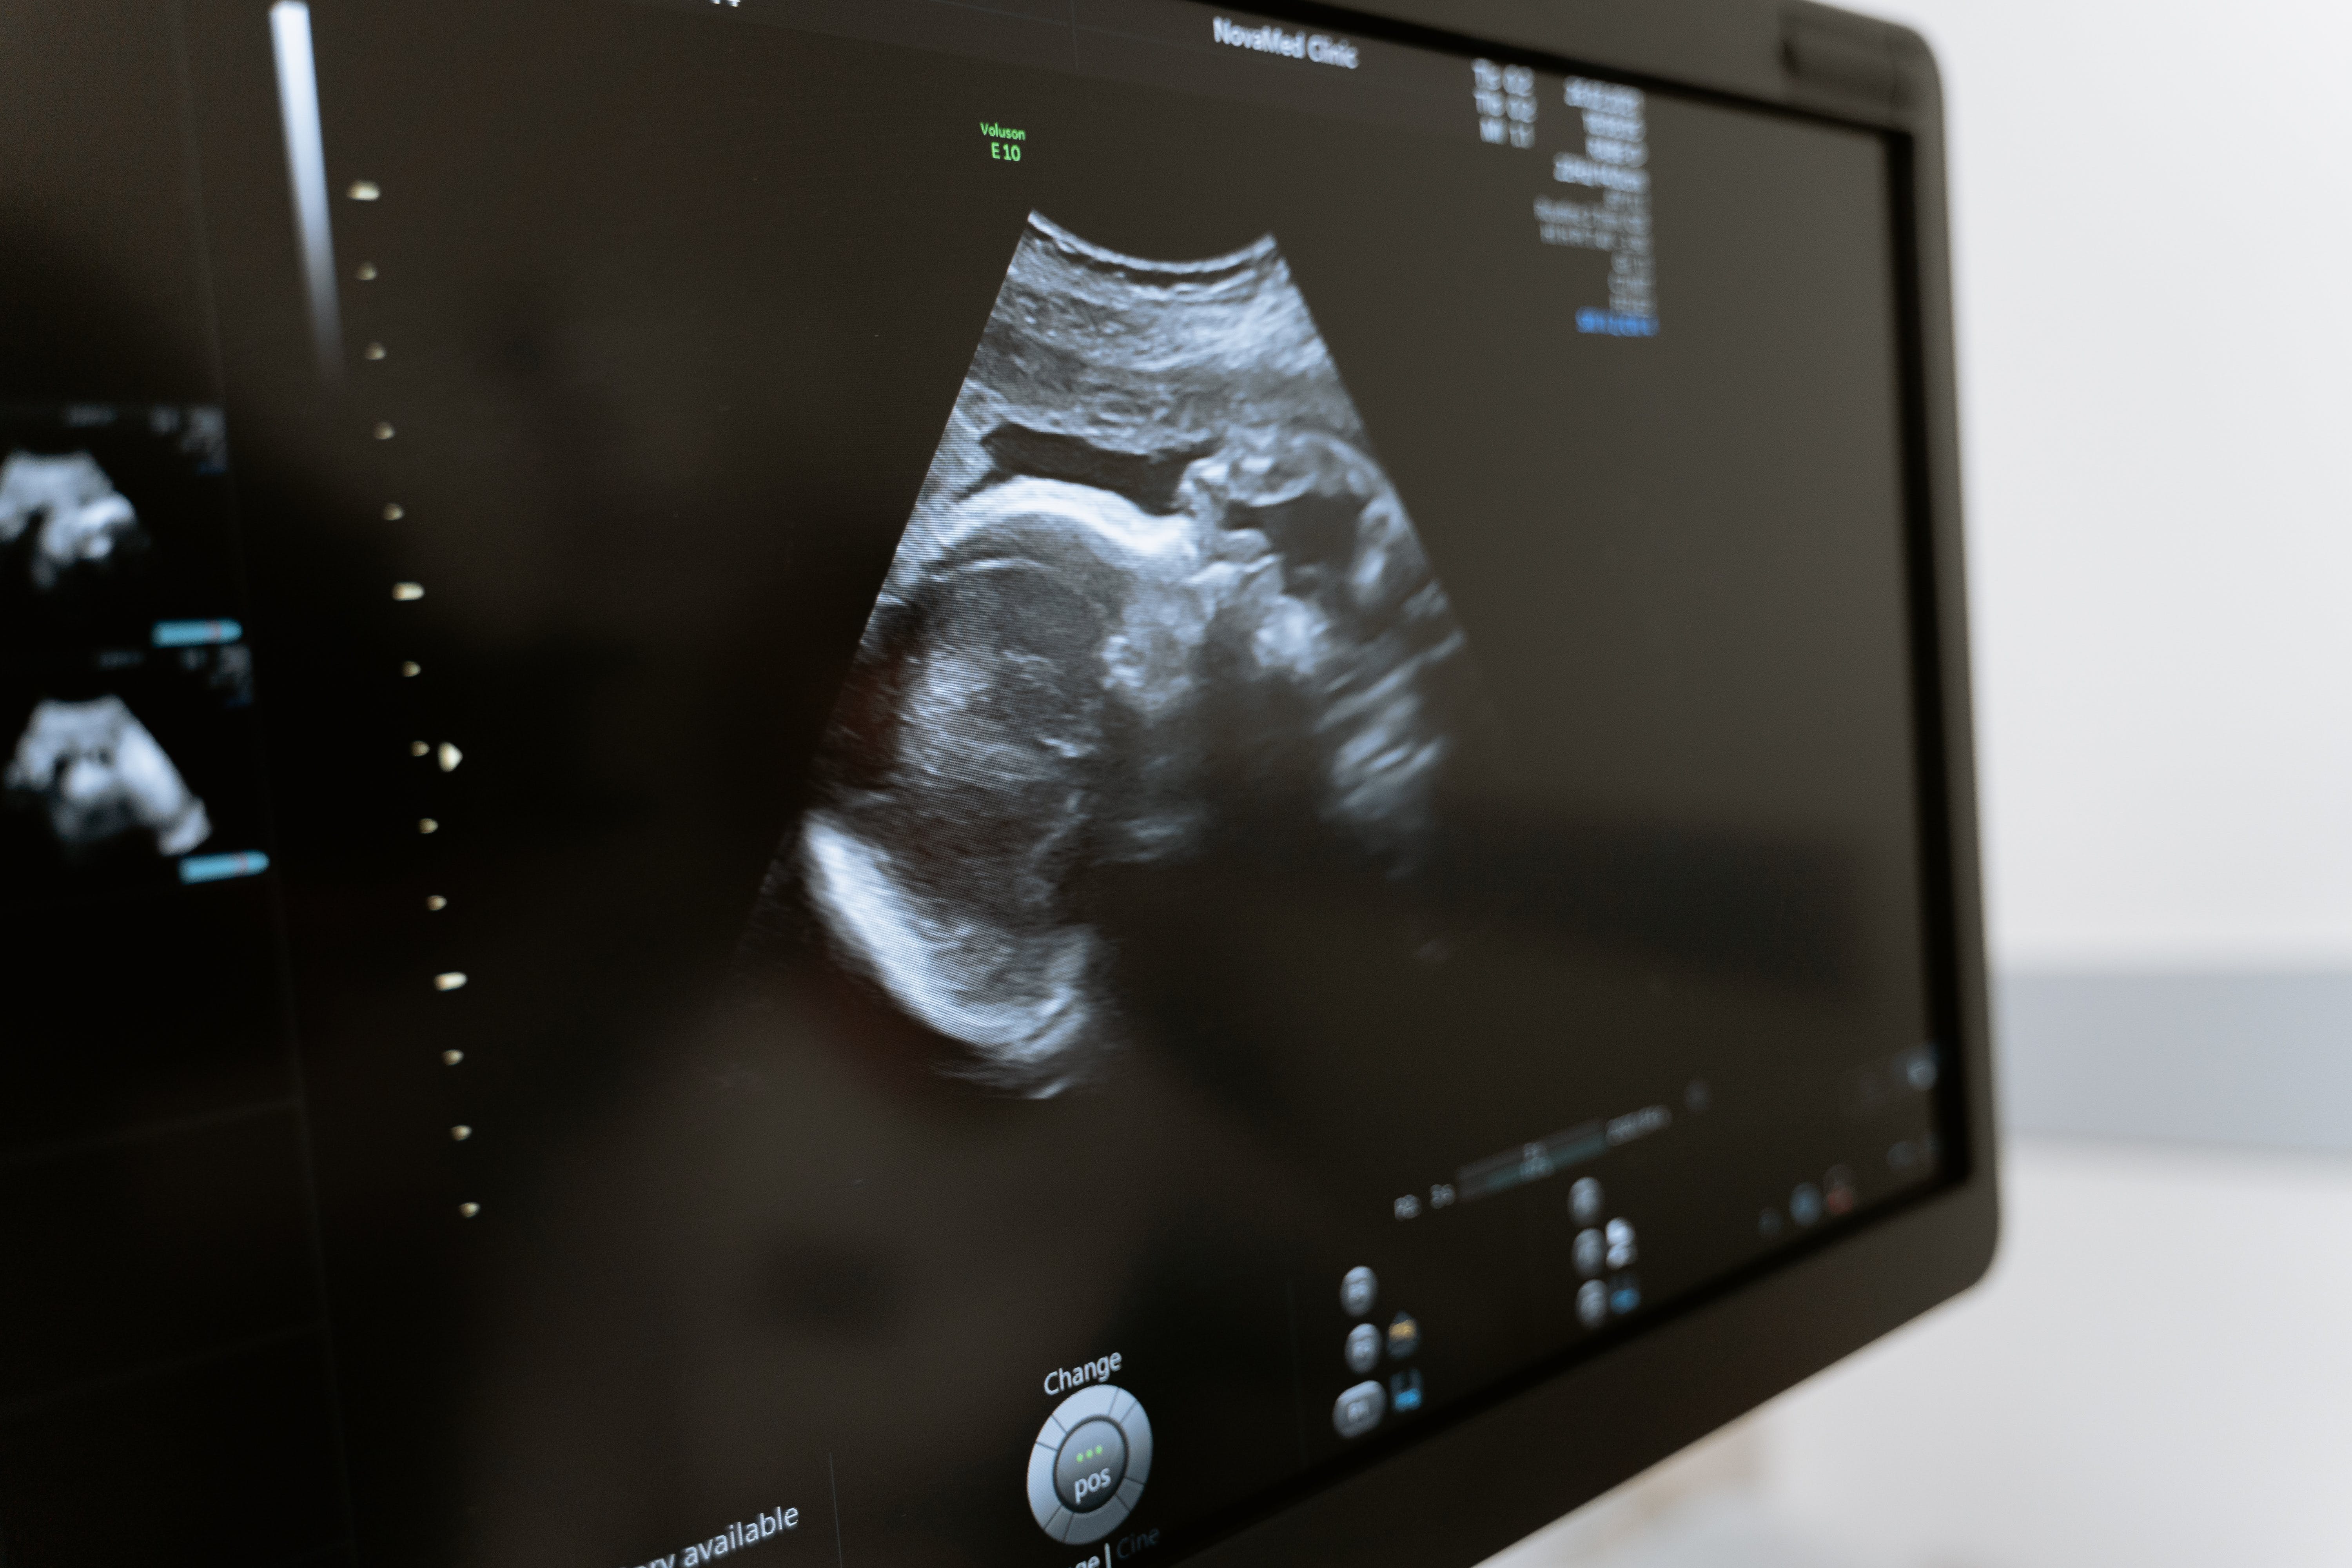

진단 여정은 종종 상세한 임상 병력으로 시작됩니다. 의료 서비스 제공자는 환자의 증상, 월경 주기 패턴 및 관련 불편 사항에 대한 정보를 수집합니다. 골반 부위의 이상이나 압통을 평가하기 위해 골반 검사를 포함한 철저한 신체검사를 실시할 수 있습니다. 초음파와 같은 영상 연구를 통해 특정 자궁내막 낭종을 식별할 수 있지만 상태의 전체 범위를 진단하는 능력에는 제한이 있습니다. 최종 진단에는 종종 자궁내막증을 식별하는 최적의 표준으로 간주되는 복강경 수술이 포함됩니다. 이 최소 침습 시술 동안 작은 절개를 통해 카메라가 달린 얇은 관을 삽입하여 자궁내막 임플란트를 시각화하고 경우에 따라 제거합니다. 자궁 외부에 자궁내막 조직이 있는지 확인하기 위해 복강경 검사 중에 조직 샘플을 채취할 수 있습니다. 통증을 해결하는 것이 자궁내막증 치료의 주요 초점입니다. 비스테로이드성 항염증제와 같은 일반의약품 진통제가 권장될 수 있습니다. 호르몬 요법은 월경주기를 억제하여 자궁내막증과 관련된 주기적인 출혈과 염증을 줄이는 것을 목표로 합니다. 옵션에는 피임약, 호르몬 IUD, GnRH 작용제가 포함됩니다. 복강경 수술은 진단 도구 역할을 할 뿐만 아니라 자궁내막 임플란트를 제거하거나 파괴할 수도 있습니다. 수술 옵션은 병변의 절제(절단)부터 심각한 경우 자궁적출술과 같은 보다 광범위한 절차까지 다양합니다. 생활방식 수정, 침술, 식이요법 변화를 포함한 보완적 접근법을 통합하여 전반적인 웰빙을 향상하고 전통적인 의료 개입을 보완할 수 있습니다.